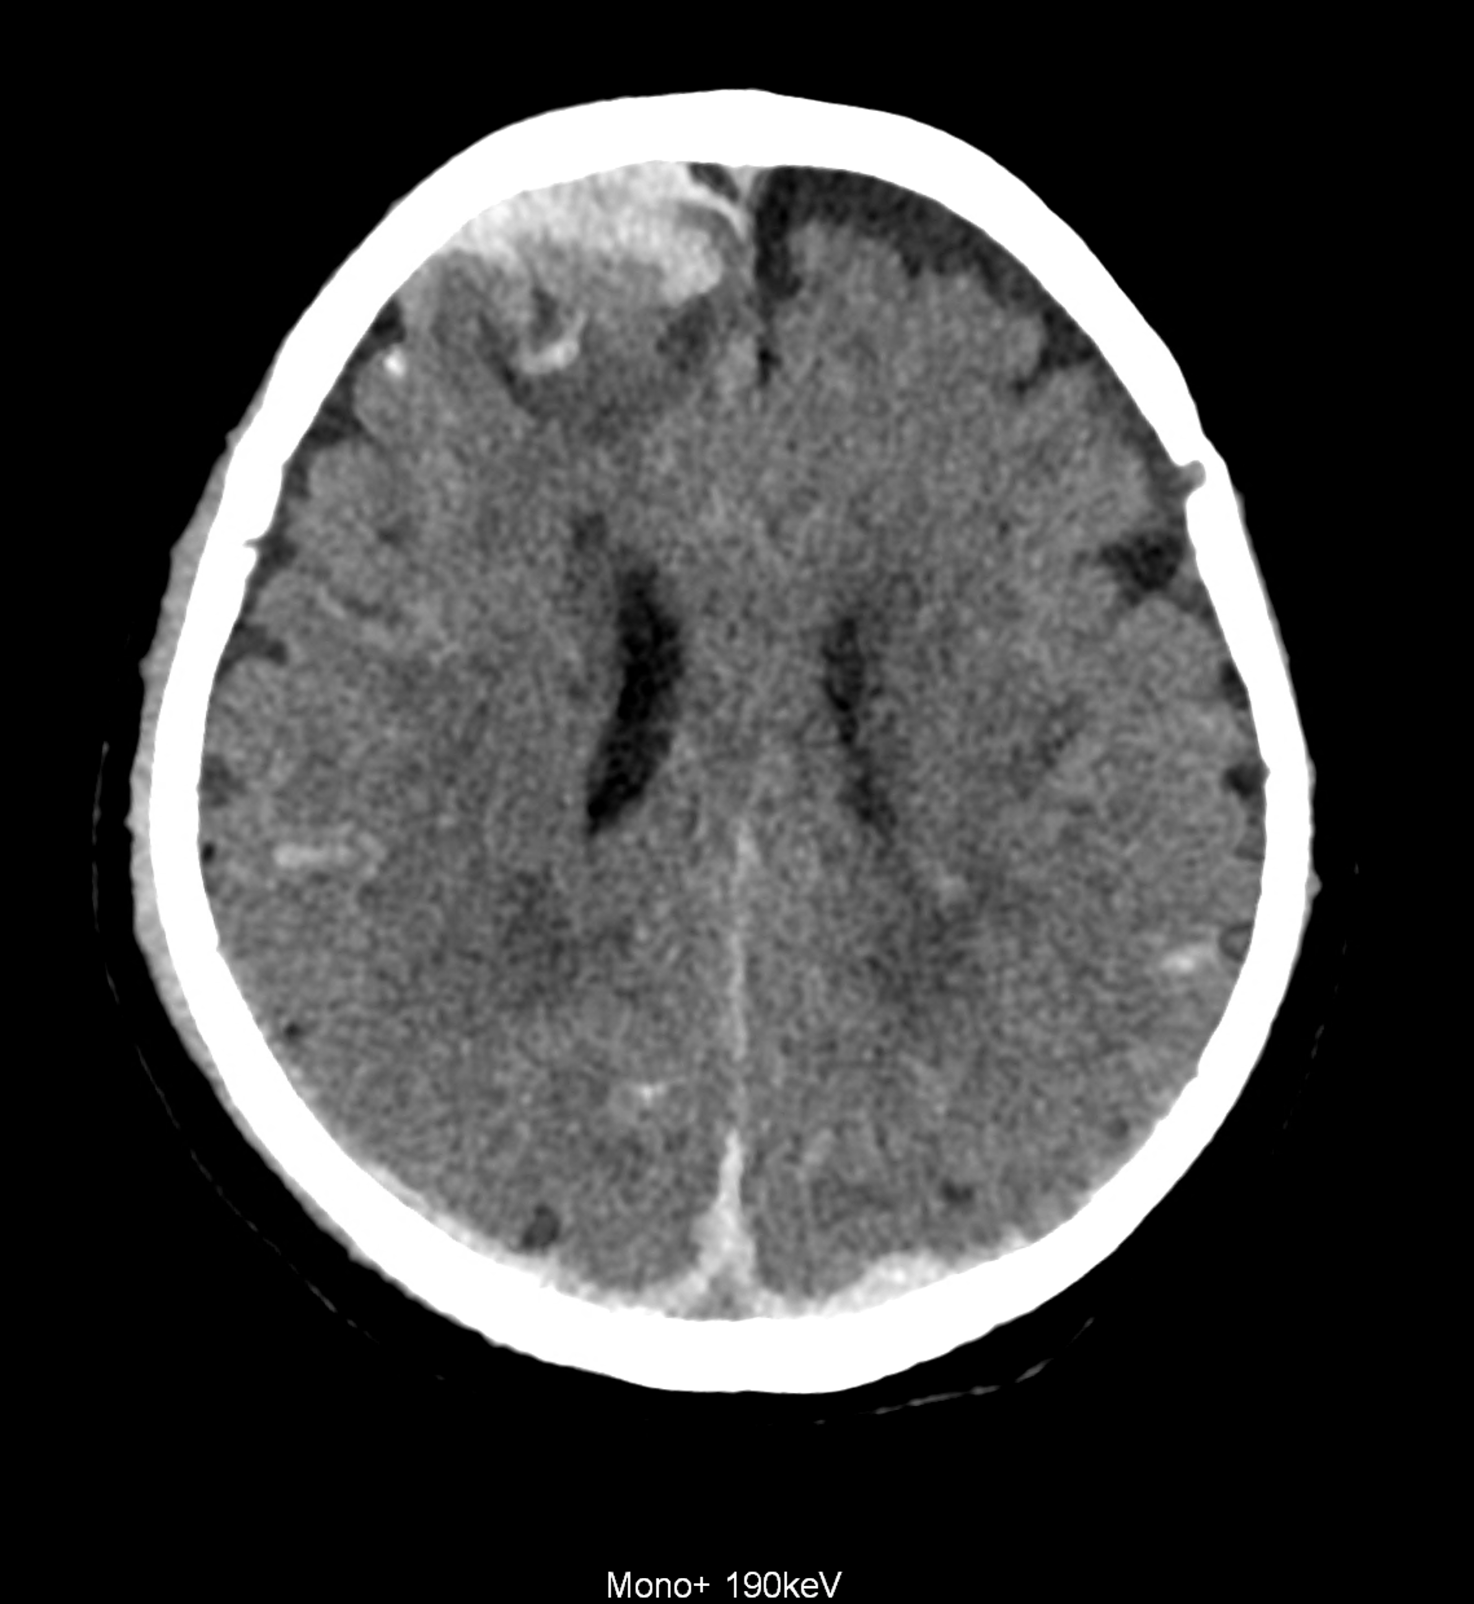

Bleeding is characterized by different absorption characteristics than healthy brain tissue (both gray and white matter) and cerebrospinal fluid. Due to the higher proportion of proteins with amino acids with disulfide bonds, the signal intensity increases at higher energies, making it possible to use monoenergetic imaging at energies above 140 keV, and/or virtual non-contrast. The hemorrhage then becomes more hyperdense, while the rest of the brain tissue acquires a uniform low signal. In addition to bleeding, areas of extracellular fluid of vasogenic origin are also imaged, i.e., in areas around contusion-type brain tissue injuries.

An example of the use of spectral imaging in complex brain injury, where contusions, diffuse axonal injury, subarachnoid hemorrhage, subdural hemorrhage, and blood in the ventricular system are present.

comparison of the images with the energies of monoenergetic reconstructions 40 keV, 67 keV (standard conventional reconstruction), 190 keV and virtual non contrast (VNC)